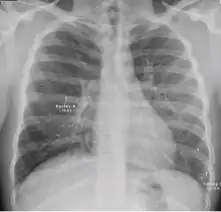

Chest x-ray showing patchy opacification on the upper right and mid-zone lung with fibrotic shadows, as well as bilateral hilar lymphadenopathy. -